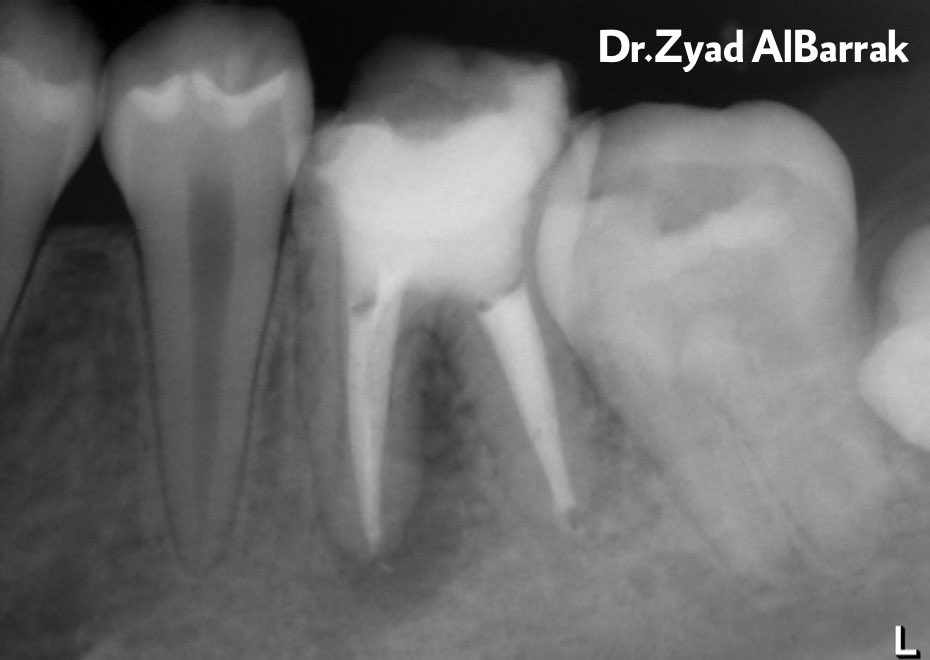

According to Ferreira, 2001

In comparison between K-Flexofiles with chloroform, Hedstrom files with chloroform, ProFiles 0.04 with chloroform, ProFiles 0.04 alone in removing the gutta-percha from obturated root canals :

-There was no statistically significant difference in canal cleanliness between K-Flexofiles and ProFiles.

-ProFiles were significantly faster than hand files.